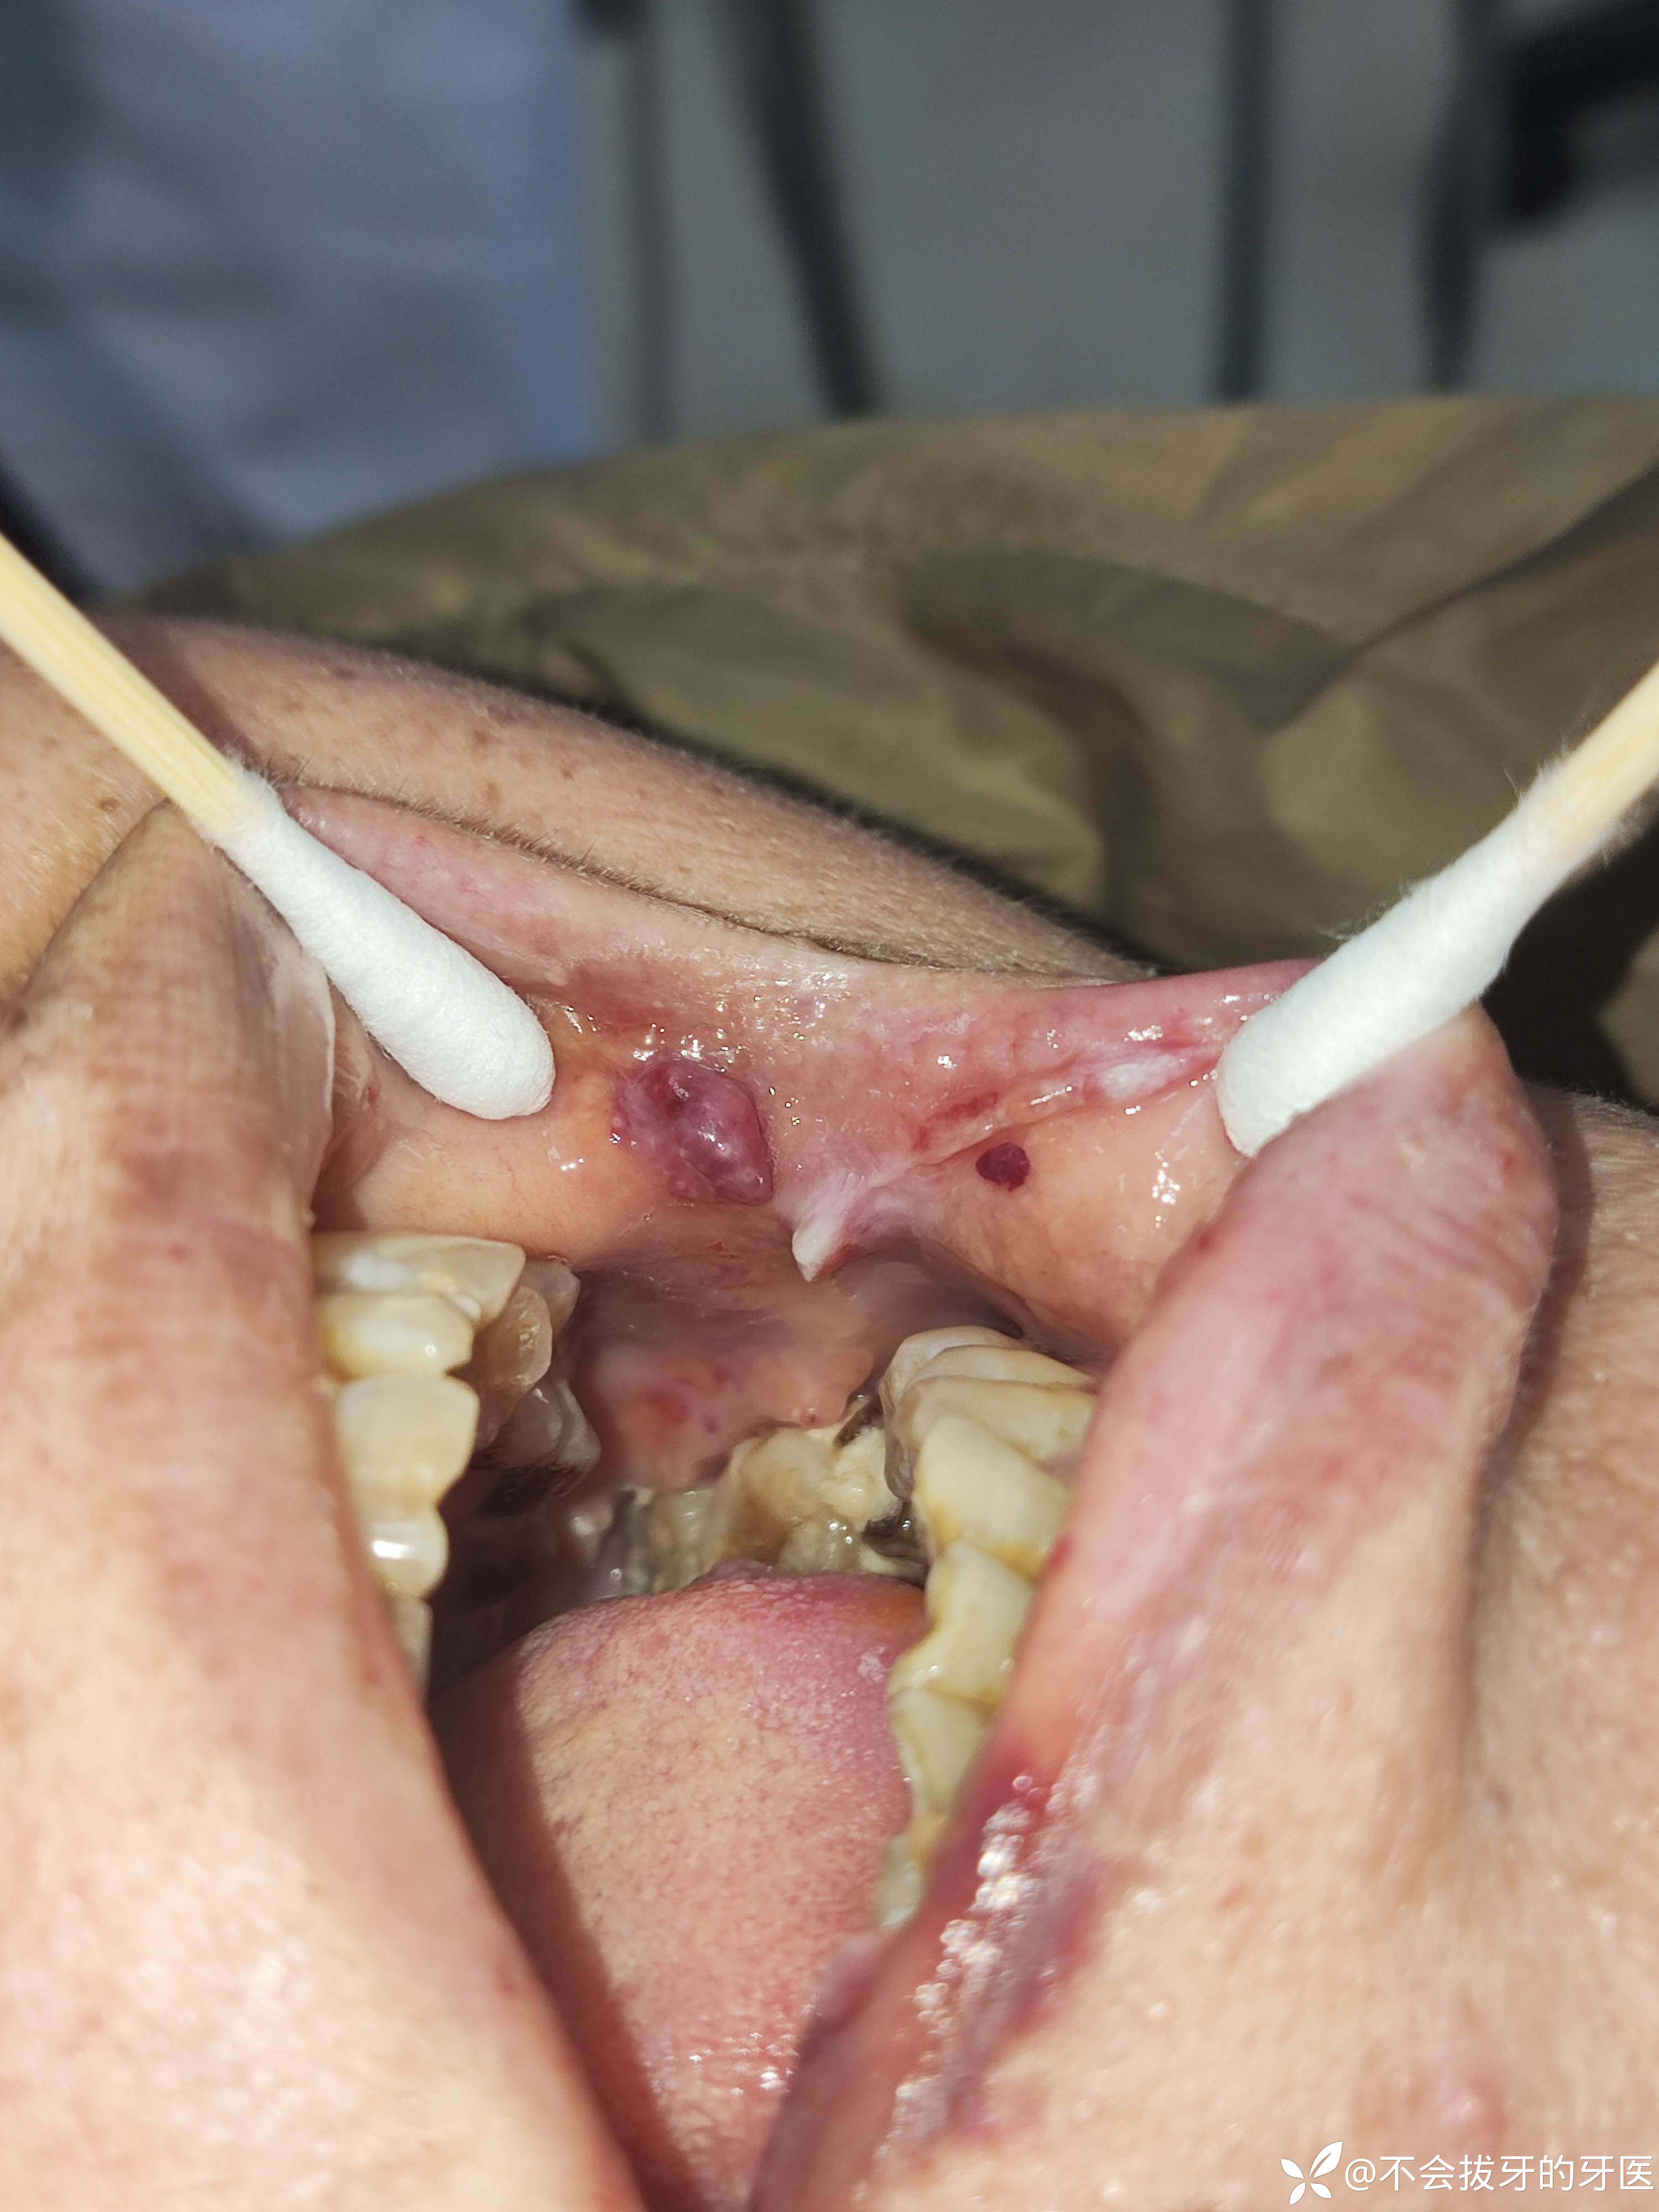

患者第一次就诊图